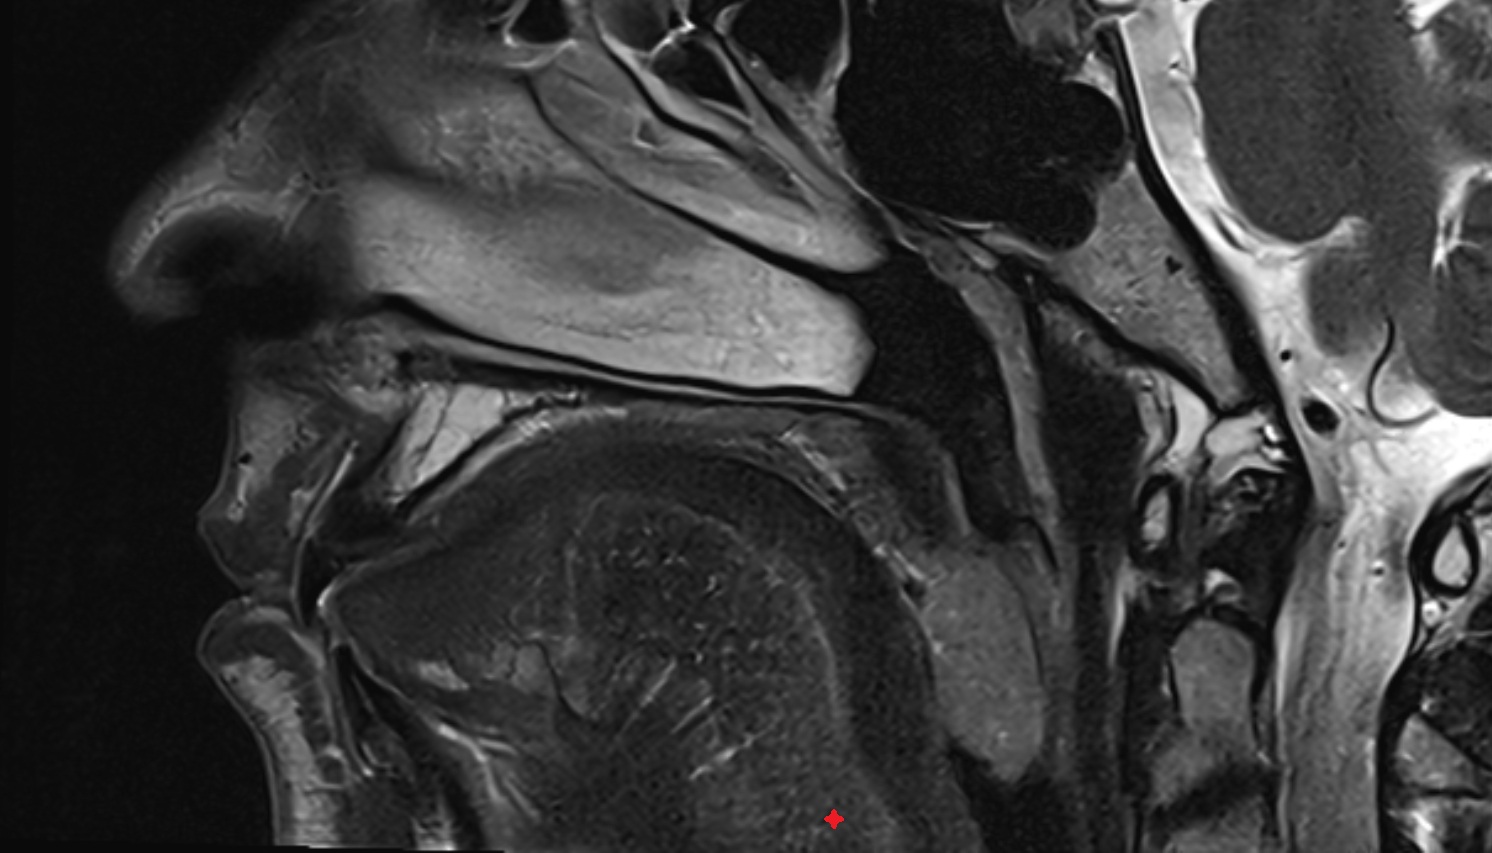

- Temporomandibular joint

- Articular disc of temporomandibular joint

- Articular eminence

- Articular surface of mandibular fossa

- Anterior Band of Articular Disc TMJ

- Posterior band of articular disc, TMJ

- Intermediate zone of articular disc

- Superior retrodiscal layer

- Superior synovial membrane of temporomandibular joint

- Mandible

- Mandibular condyle

- Mandibular fossa

- Neck of mandible

- Superior head of lateral pterygoid muscle

- Inferior head of lateral pterygoid muscle